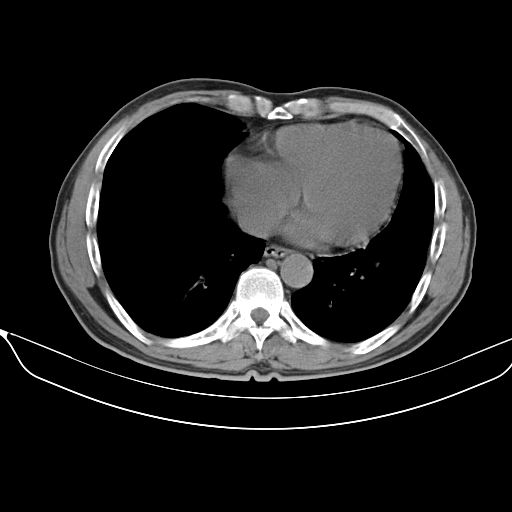

以下是引用shuiyuan在2010-3-1 10:45:00的发言:[br]考虑左肺上叶中心型肺癌伴阻塞型炎症,邻近胸膜受侵。

以下是引用心路寻觅在2010-3-1 10:23:00的发言:[br]1、考虑左肺上叶周围型肺癌[br]2、右上肺陈旧性病灶。[br][br][本贴已被 心路寻觅 于 2010-3-1 10:40:18 修改过]